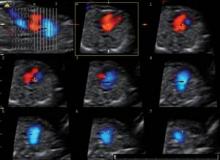

Figure 3. 3-D blocks analyzed by tomographic section in a systematic approach, yield complete catalogue of anatomic cardiac landmarks in over 80% of fetuses at 12 weeks.

Indeed, significant improvements in the overall computing capability of modern ultrasound equipment, in three-dimensional color ultrasonography, and in ultrasound image resolution – as well as specific new technologic developments such as tomographic imaging and spatiotemporal image correlation – have opened the door to first-trimester cardiac screening.

In the majority of patients, up to 12 parameters of fetal cardiac structure can be visualized. Each of the three segments of the exam takes only a few seconds to perform, so the actual collection of information is rapid. The technologic advances have also made the acquisition of images easier and less operator dependent. Moreover, the analysis is then performed offline, so the mother can go home afterward. Offline analysis of images also means that the ultrasound scan itself can be performed by trained sonographers at a distance from a cardiac center, with the information transmitted to the center for expert analysis.